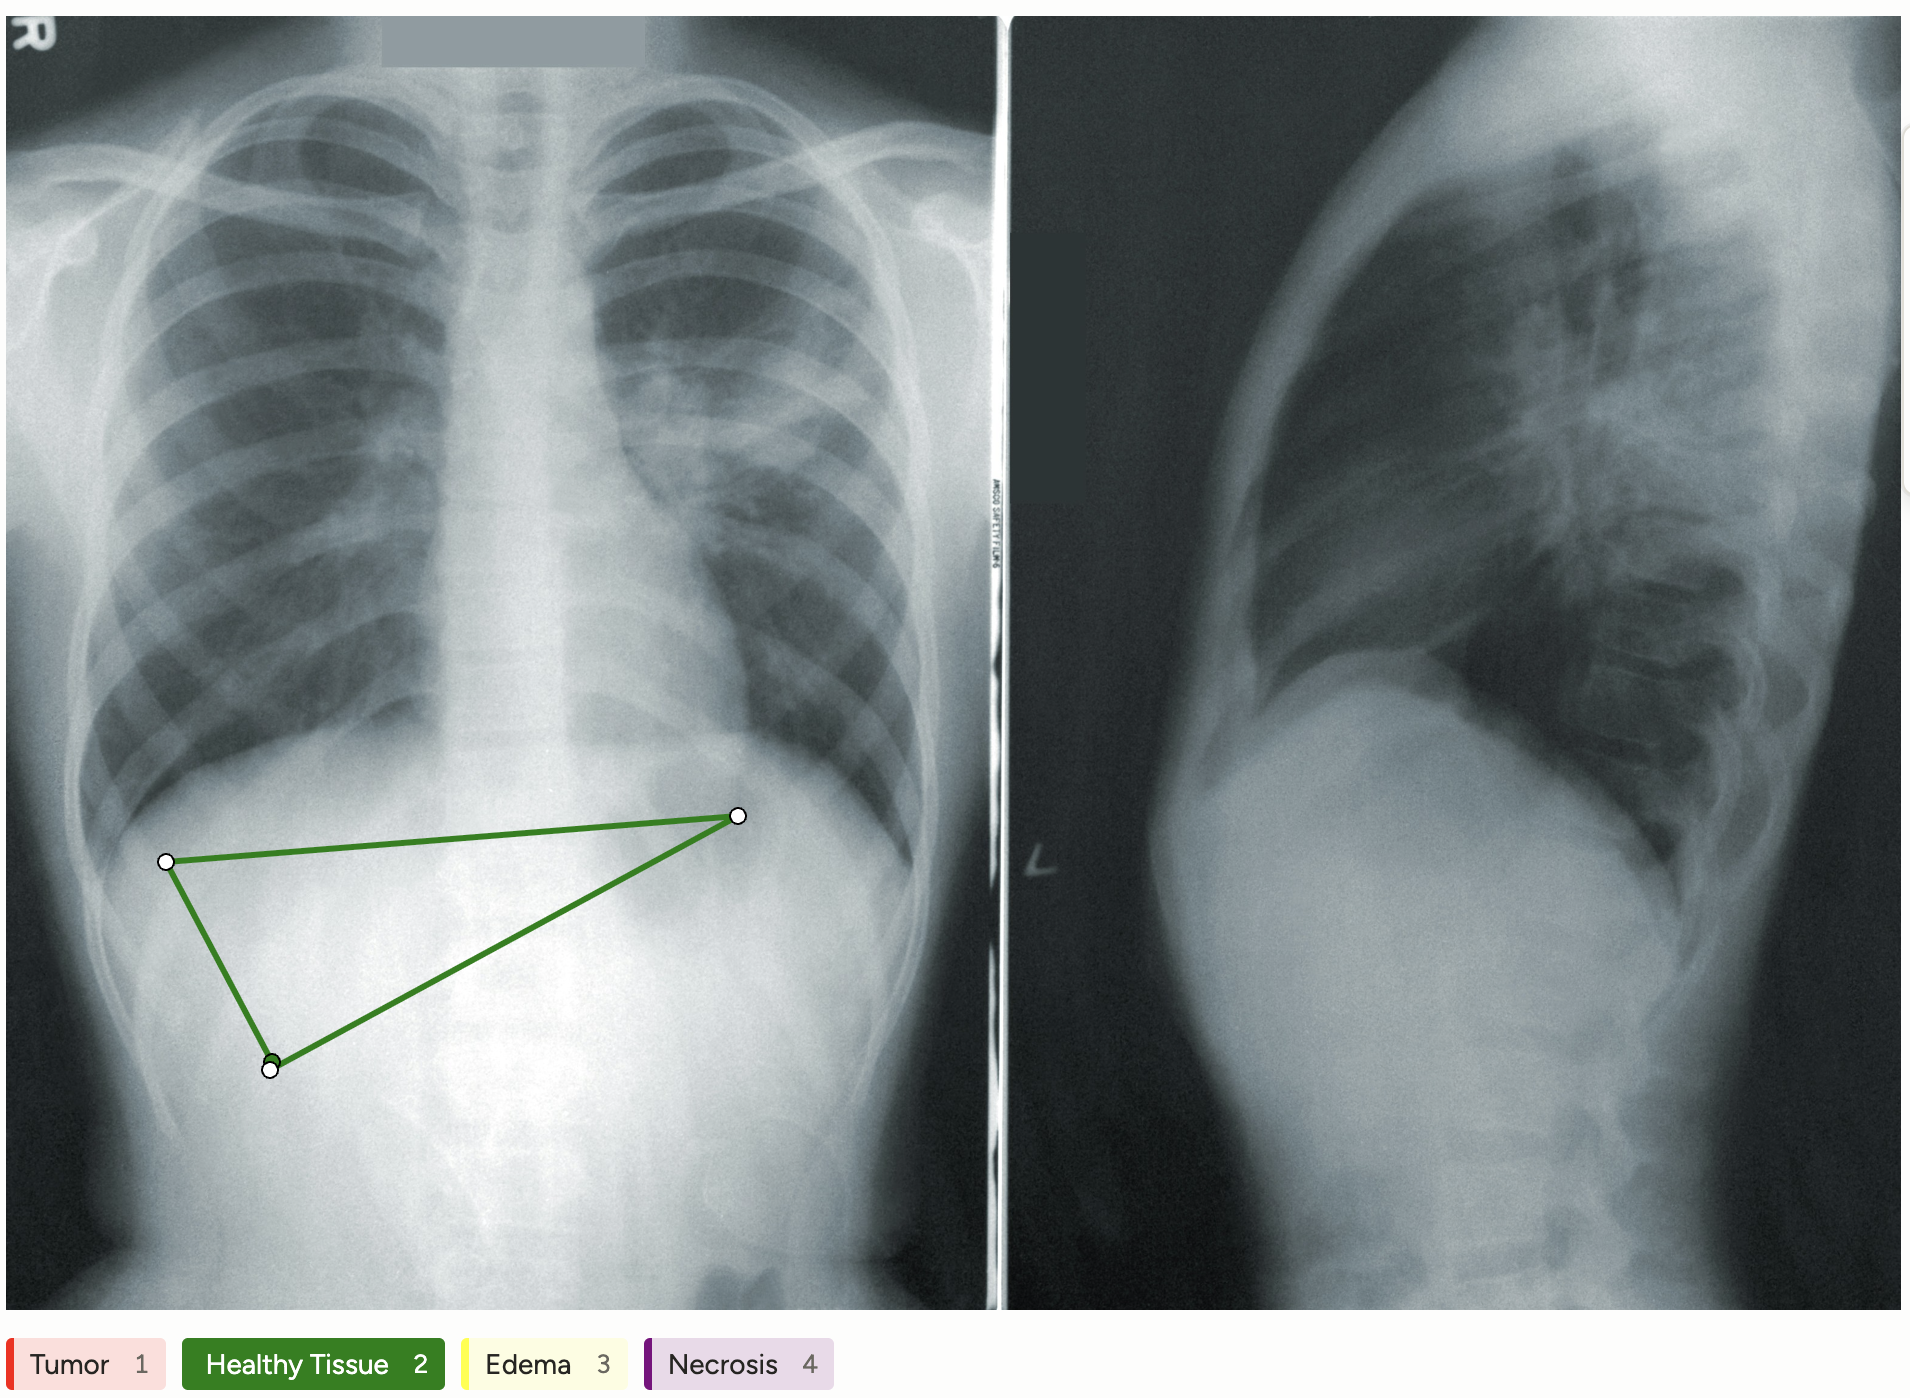

Semantic segmentation with polygons in medical image analysis is essential for accurately identifying and delineating anatomical structures in complex images, such as tumors or organs, which directly impacts diagnostics and treatment planning. The AI model harnesses this data to automate the interpretation of medical images, enhancing both clinician efficiency and accuracy in patient care.

This configuration allows annotators to select a tissue type and accurately delineate its boundaries directly on the medical image, enabling precise semantic segmentation of different anatomical and pathological regions.

Use the PolygonLabels control tag to allow annotators to delineate polygonal regions corresponding to specific tissue types or pathological areas.

Annotators can control the opacity of the polygons using the opacity argument, and the styling of the polygon tool using the pointSize and strokeWidth arguments. Use the background argument with the Label control tag to assign distinct colors for each tissue or pathology label.